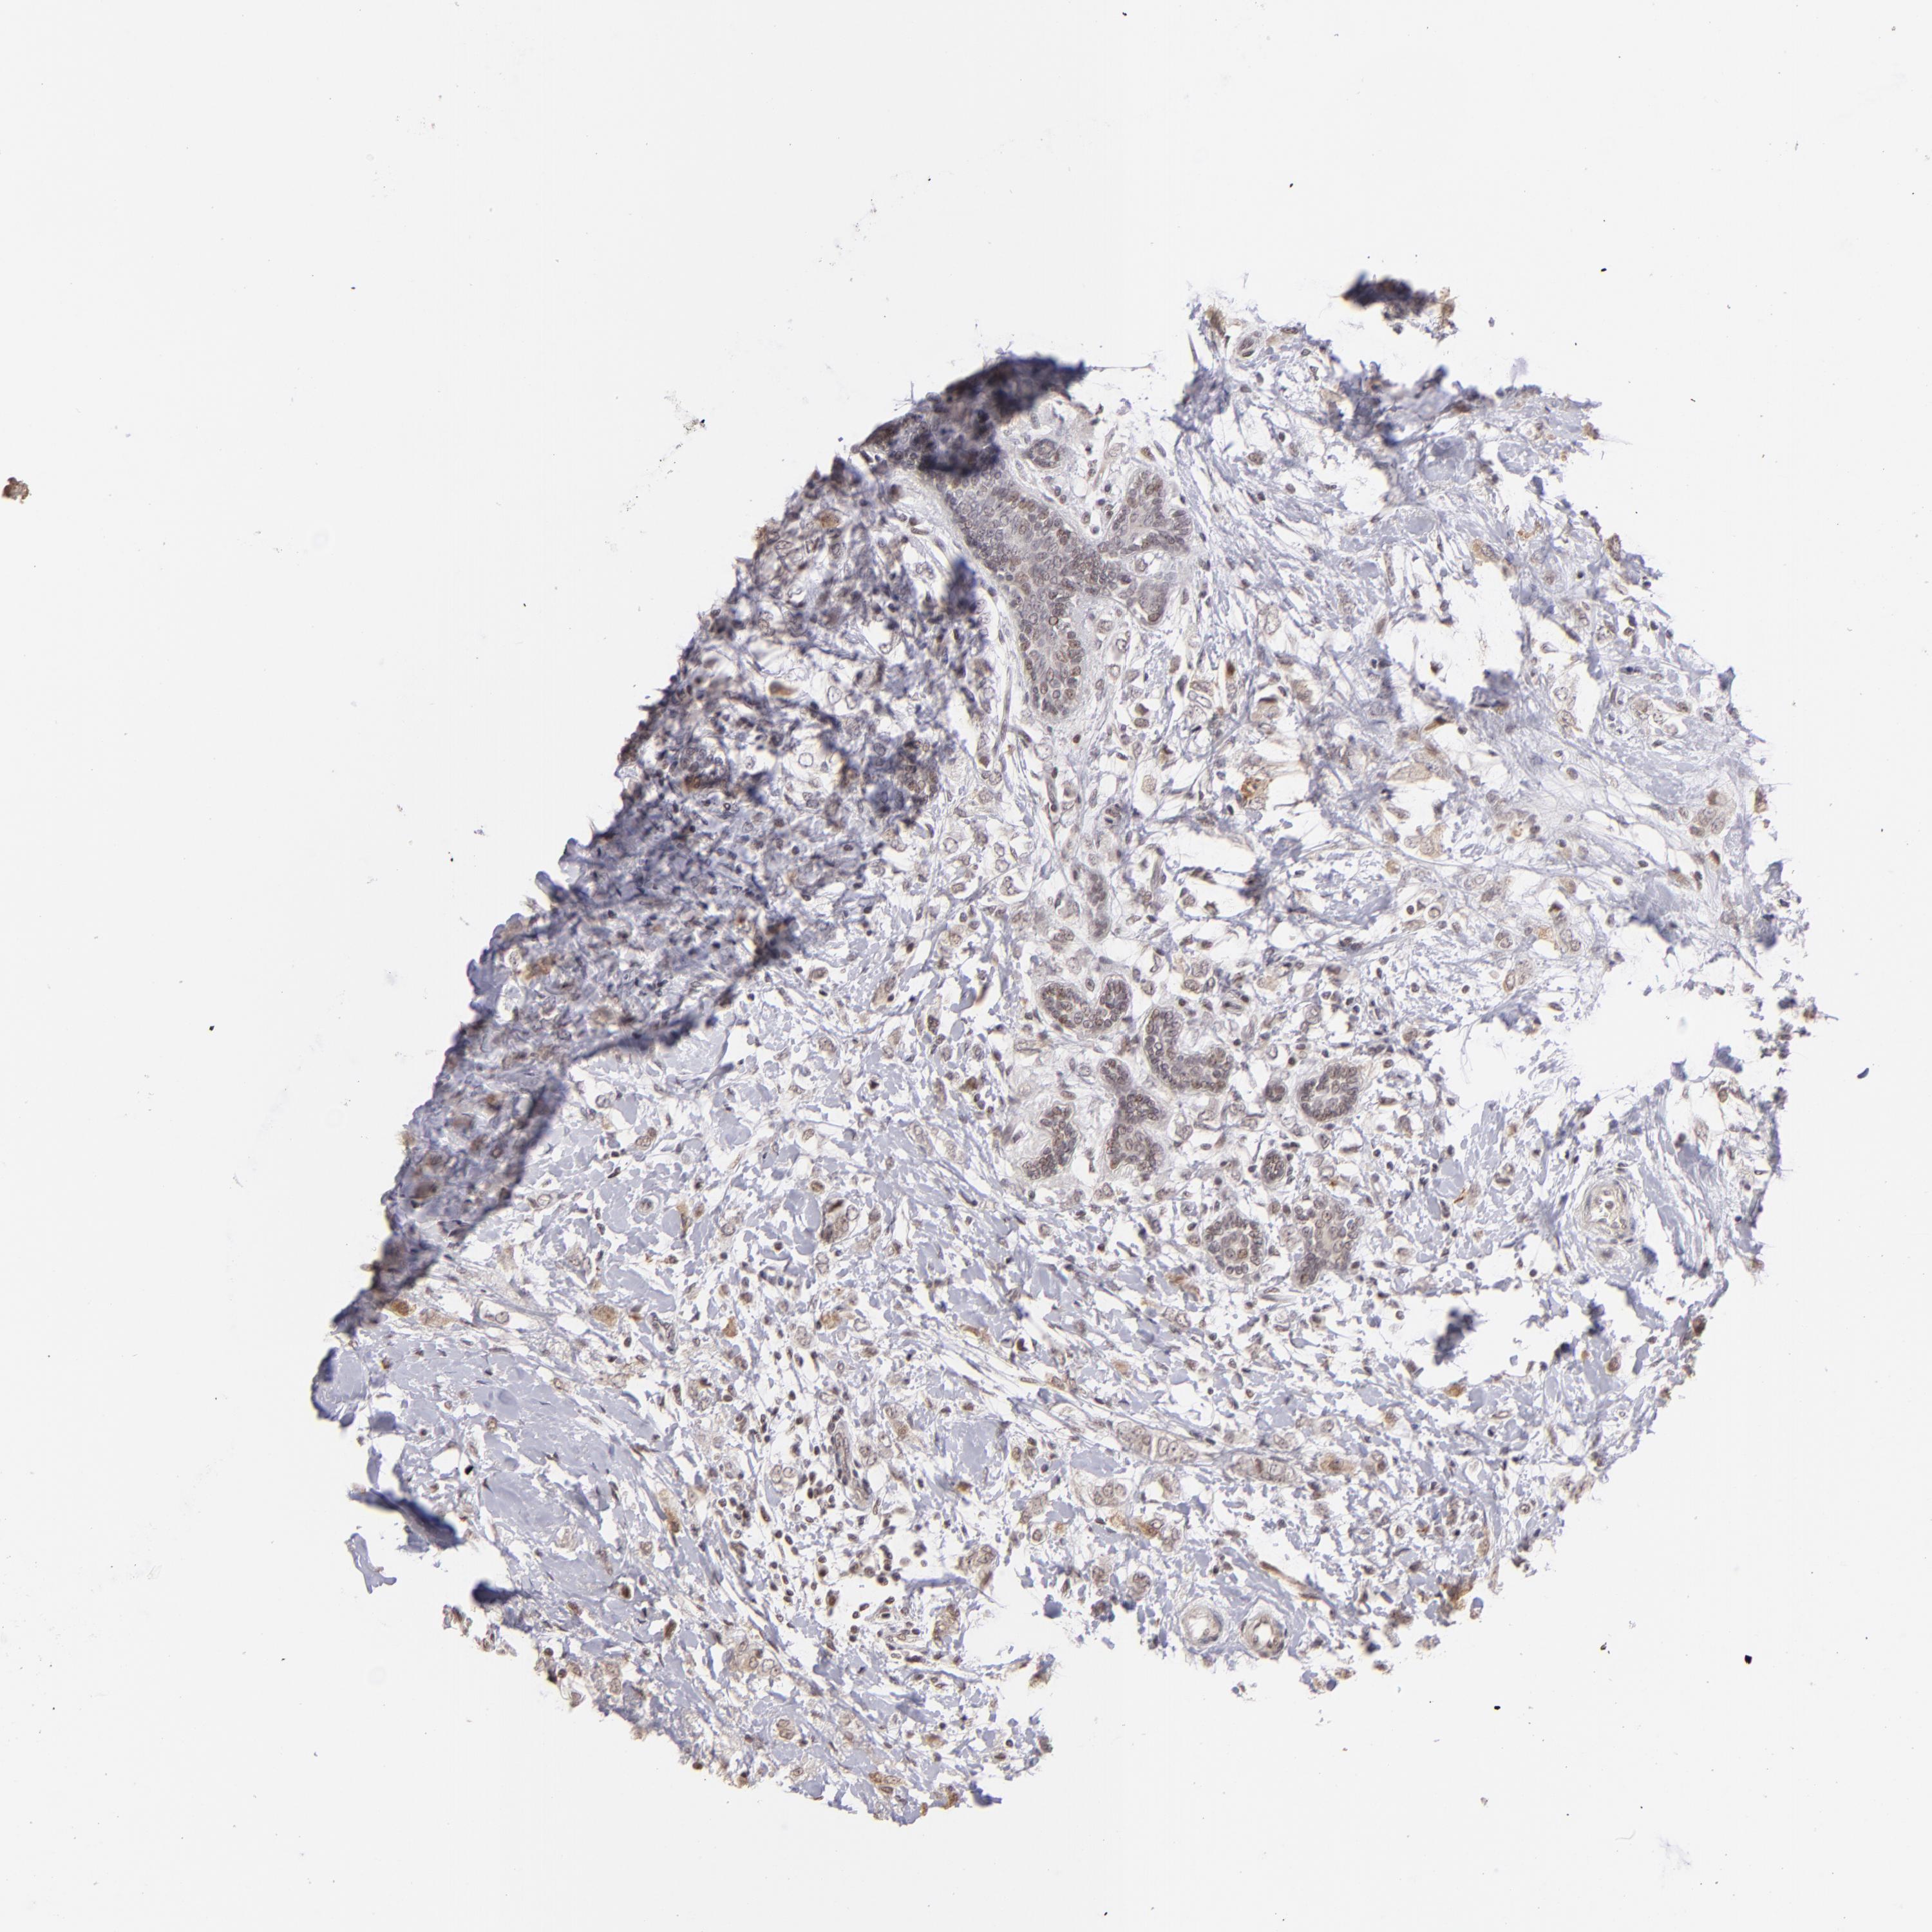

CANCER BREAST CANCER Show tissue menu

BRCA TCGA BRCA VALIDATION PROTEIN EXPRESSION

ANTIBODIES

AND

VALIDATION